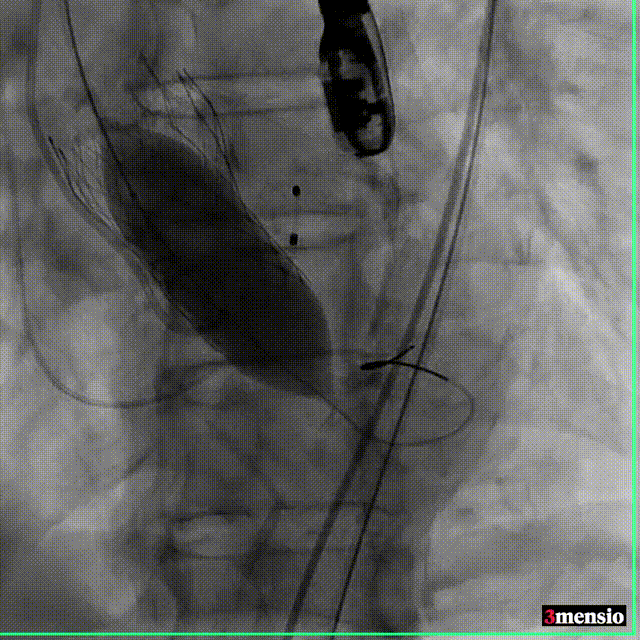

根部造影

跨瓣

20mm球囊预扩